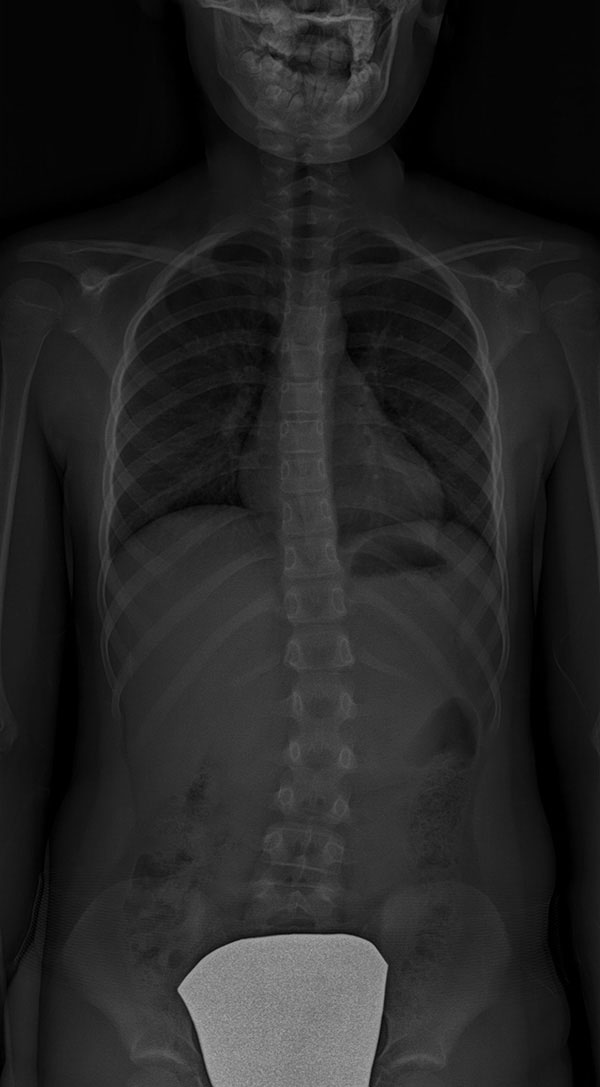

Scoliose thoracique (dorsale) – située dans la région de la colonne vertébrale où se trouvent les côtes.

![]() |